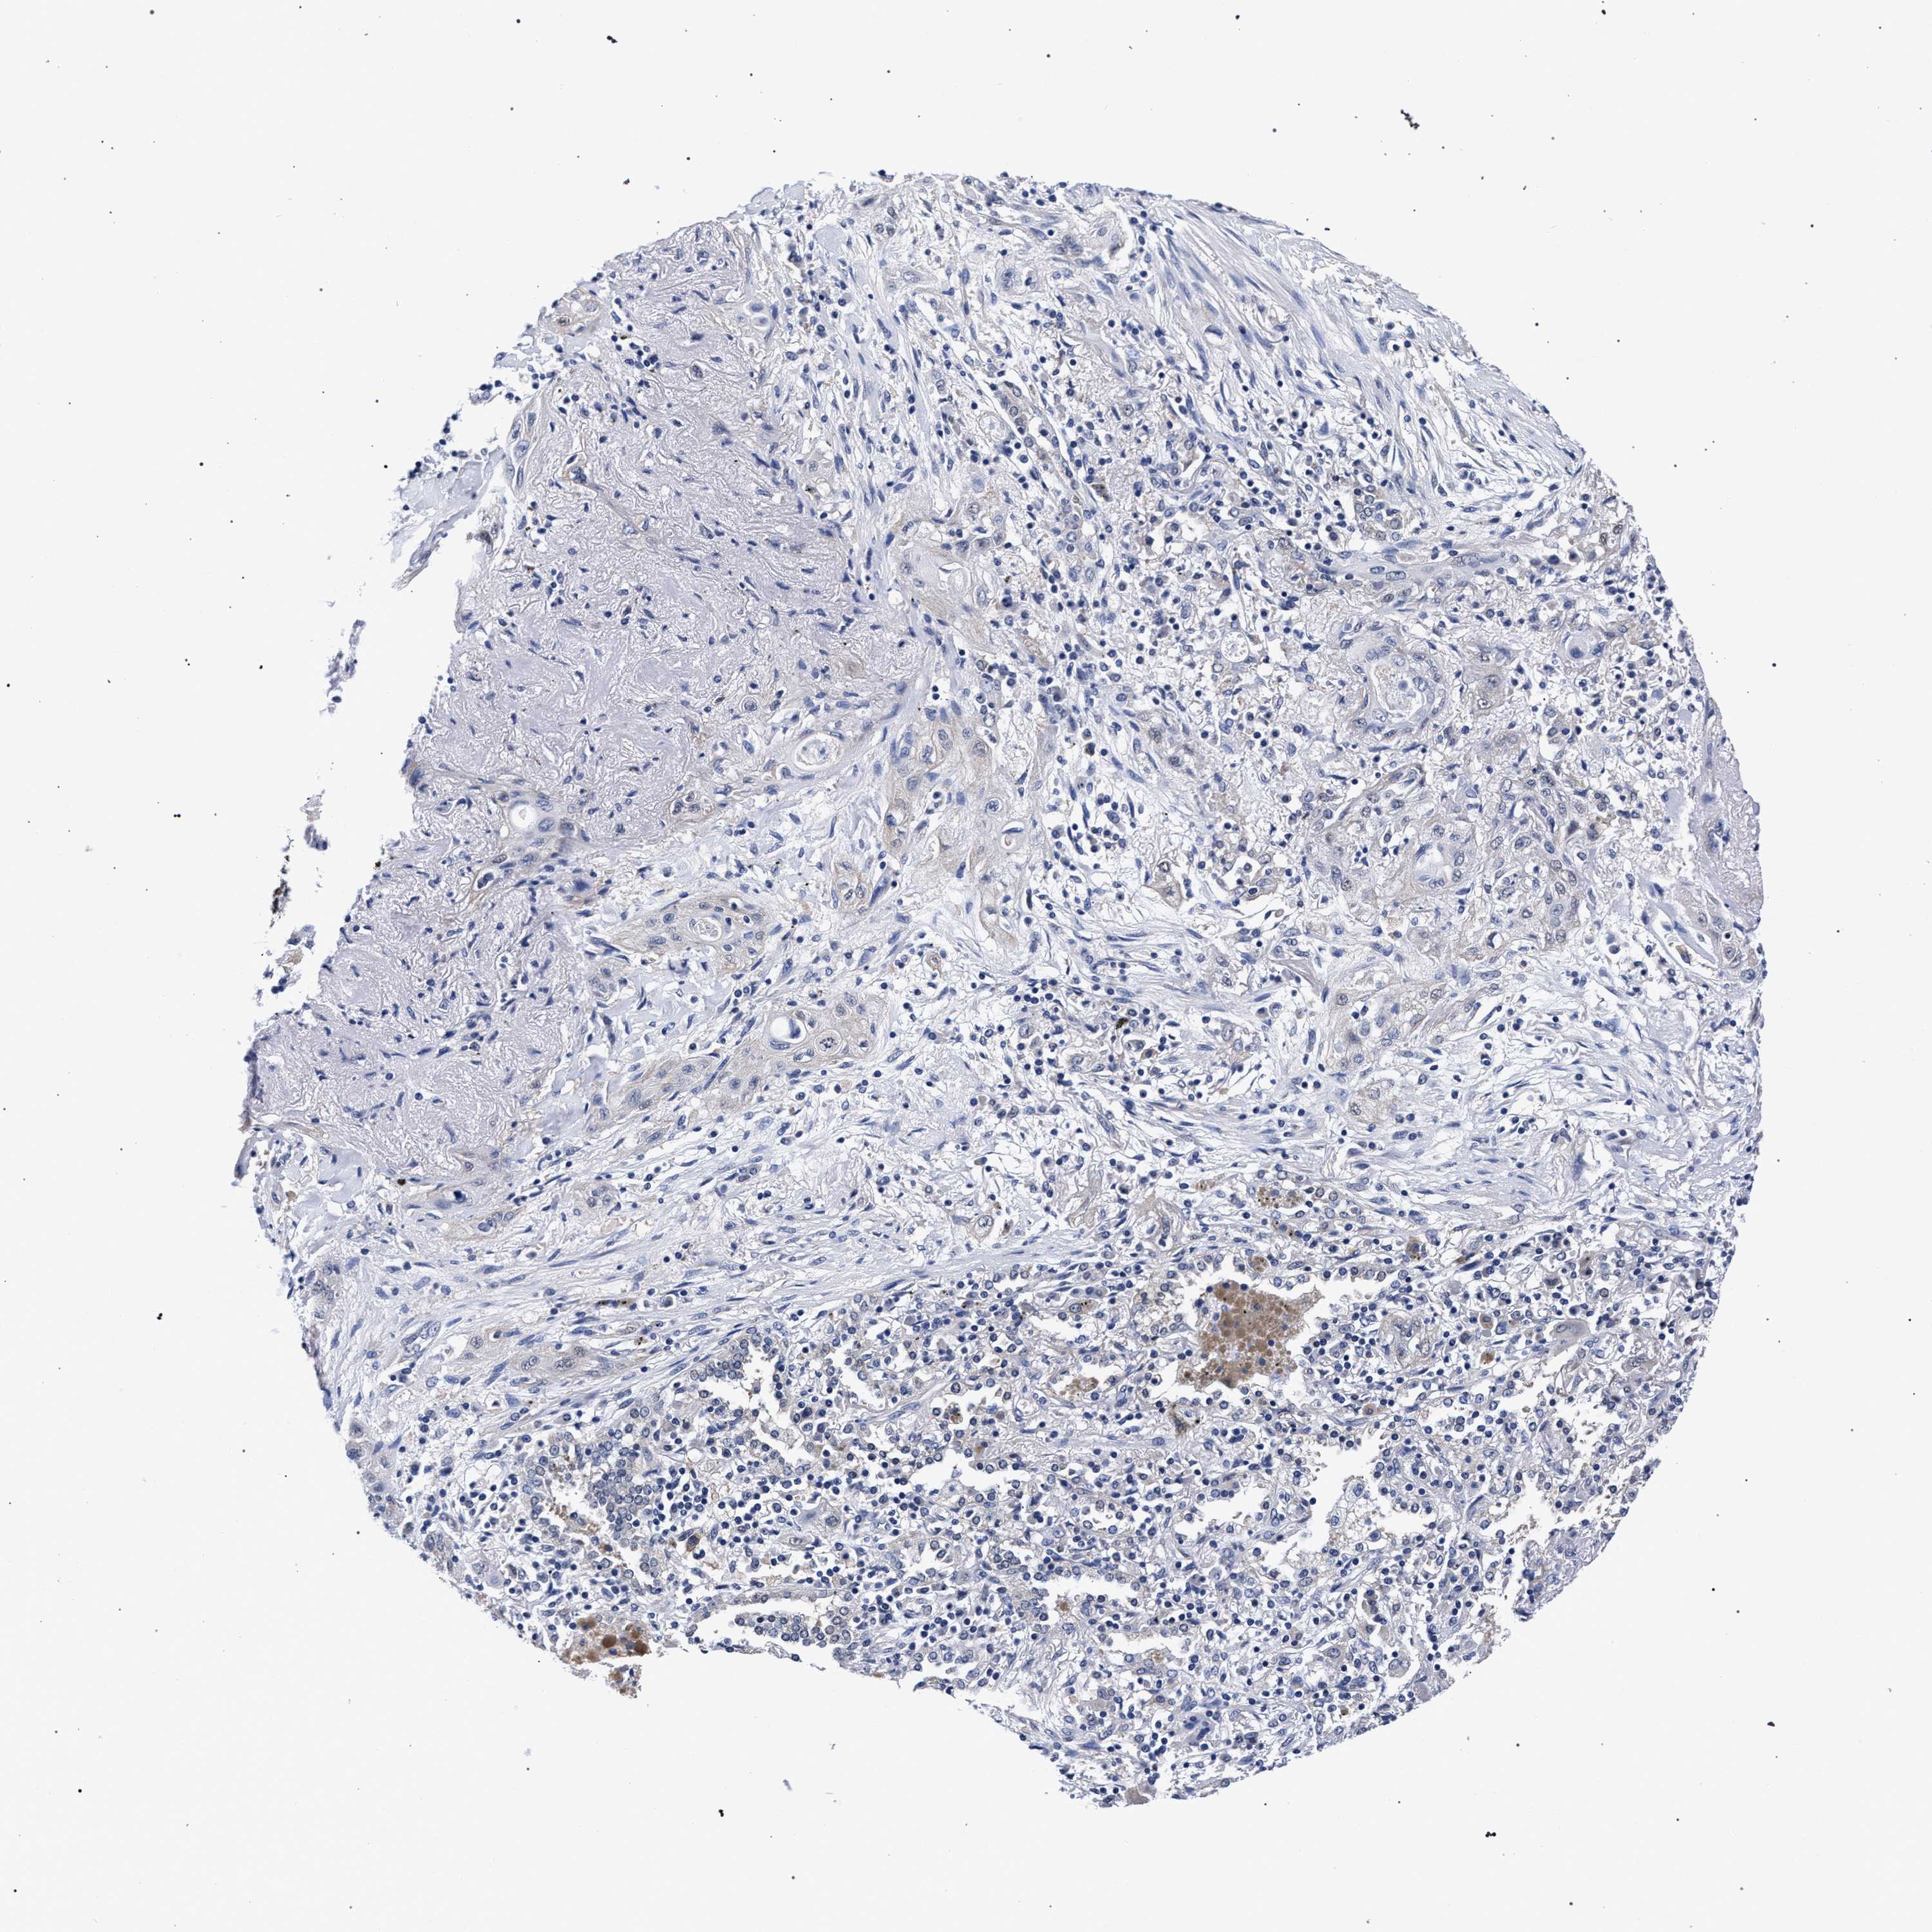

CANCER LUNG CANCER Show tissue menu

Lung cancer

Human cancer

Lung adenocarcinoma

Lung squamous cell carcinoma